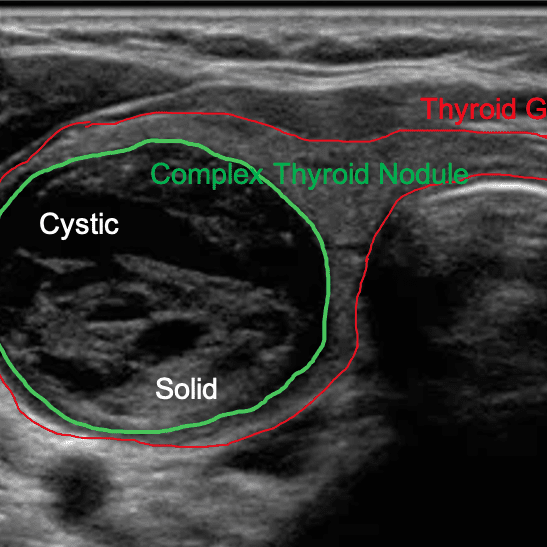

Your thyroid gland is like a thermostat that regulates your body's temperature. However, if produces too much or too little thyroid hormone, it can leads to various health issues.

Thyroglobulin Antibodies (TgAb)

This test checks for antibodies created against thyroglobulin, a protein produced and used by the thyroid gland to make T3 and T4 hormones, which control metabolism and tissue/cell growth. If present, it may indicate thyroid-related autoimmune disorders, such as Hashimoto’s.

Thyroid Peroxidase Antibodies (TPO)

This test checks for elevated antibodies created against thyroid peroxidase (TPO), an enzyme that helps produce hormones. Therefore, if antibodies are detected with this test, it can indicate thyroid-related autoimmune disorders, such as Hashimoto’s. Comparing this test with abnormal levels of thyroid-stimulating hormone may indicate Graves’ disease.

Thyroid-Stimulating Hormone (TSH)

About 1 in 5 women and 1 in 10 men have hypothyroidism, and a TSH test can help reveal thyroid issues. Looking at abnormal TSH results alongside thyroid peroxidase (TPO) may be a sign of Graves’ disease. TSH is produced by the pituitary gland and controls the release of thyroid hormones: triiodothyronine (T3) and thyroxine (T4).

Thyroxine (T4) Free

This test is typically cross-referenced with TSH and T3 to gain insight into overall thyroid function. Thyroxine, or T4, is produced in the thyroid then released into the bloodstream where it travels to the liver and kidneys. It is converted into the hormone triiodothyronine (T3). The synergy of T4 and T3 is important for heart and digestive function, metabolism, brain development, bone health, and muscle control.

Triiodothyronine (T3) Free

T3 levels can reveal an overactive (hyperthyroidism) or underactive (hypothyroidism or Hashimoto’s) thyroid. T3 is the most powerful thyroid hormone in the body. It helps regulate body temperature, control heart rate, lower cholesterol, improve memory, promote regrowth after hair loss, soothe muscle aches, regulate bowel movements, and support fertility.

Iodine

Iodine levels give insight into thyroid health. The thyroid gland absorbs iodine to produce T4 and T3 hormones, to prevent goiters and help the body make protein and use oxygen. *This add-on test is available for an additional cost and is not included in the basic membership.

Selenium

Selenium looks into the health of the liver, thyroid hormones, and kidneys. Selenium is a trace mineral found in soil that helps the body produce the antioxidant glutathione, which alleviates oxidative stress. It also stimulates thyroid hormones that aid in heart and digestive function, metabolism, brain and bone health, and muscle control. *This add-on test is available for an additional cost and is not included in the basic membership.

Hypothyroidism

This is a condition characterized by an underactive thyroid gland failing to produce sufficient thyroid hormones, leading to a wide range of health issues including fatigue, weight gain, depression, cardiovascular problems, and impaired metabolic functions